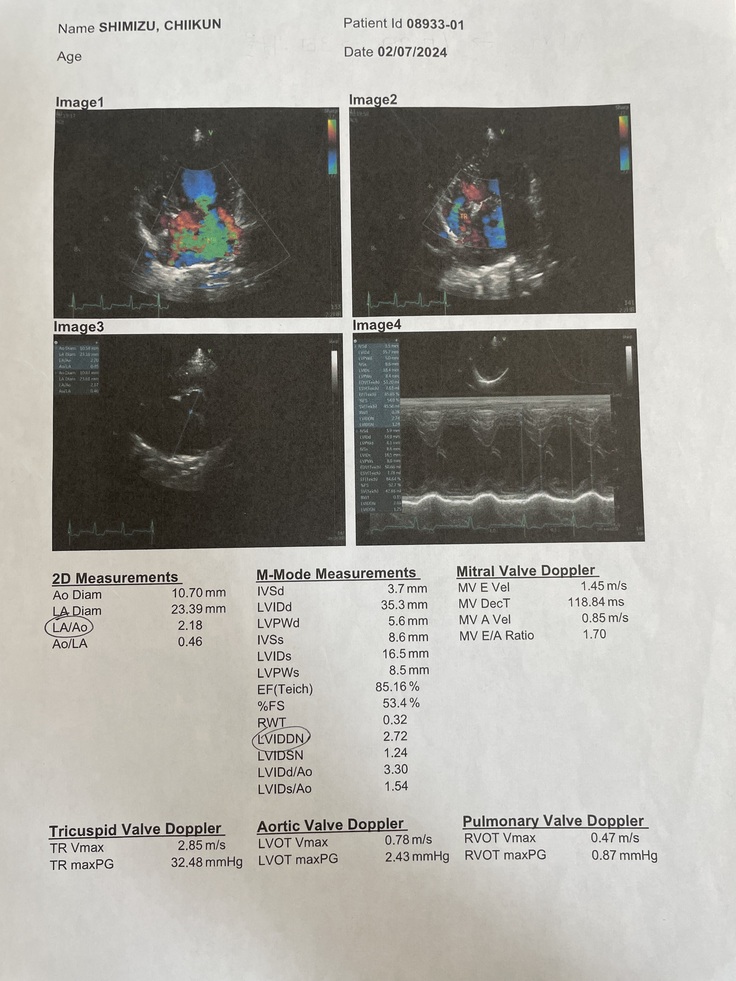

▼心臓のエコー画像

▼後日送って貰った診断書

●僧帽弁閉鎖不全症

心臓が全身に血液を送り出すポンプの役目をしており、静脈から右心房、右心室、肺へ循環し、肺で酸素を取り込んだ後、左心房、左心室、大動脈を通って全身に送り出されます。心臓には血液の逆流を防ぐための弁が四つあり、その一つが左心房と左心室の間にある僧帽弁です。僧帽弁閉鎖不全症は、左心室から送られる血液が前方(大動脈)に向かわず、一部が後方(左心房)に逆流する病気です。その結果、左心房の圧が上昇して肺のうっ血が起こり、心不全や肺水腫(肺に水が貯まる)など呼吸困難が起ます。最悪の場合、左心房の壁が破れ、心臓の外に血液が漏れ出て急死することもある危険な病気です。